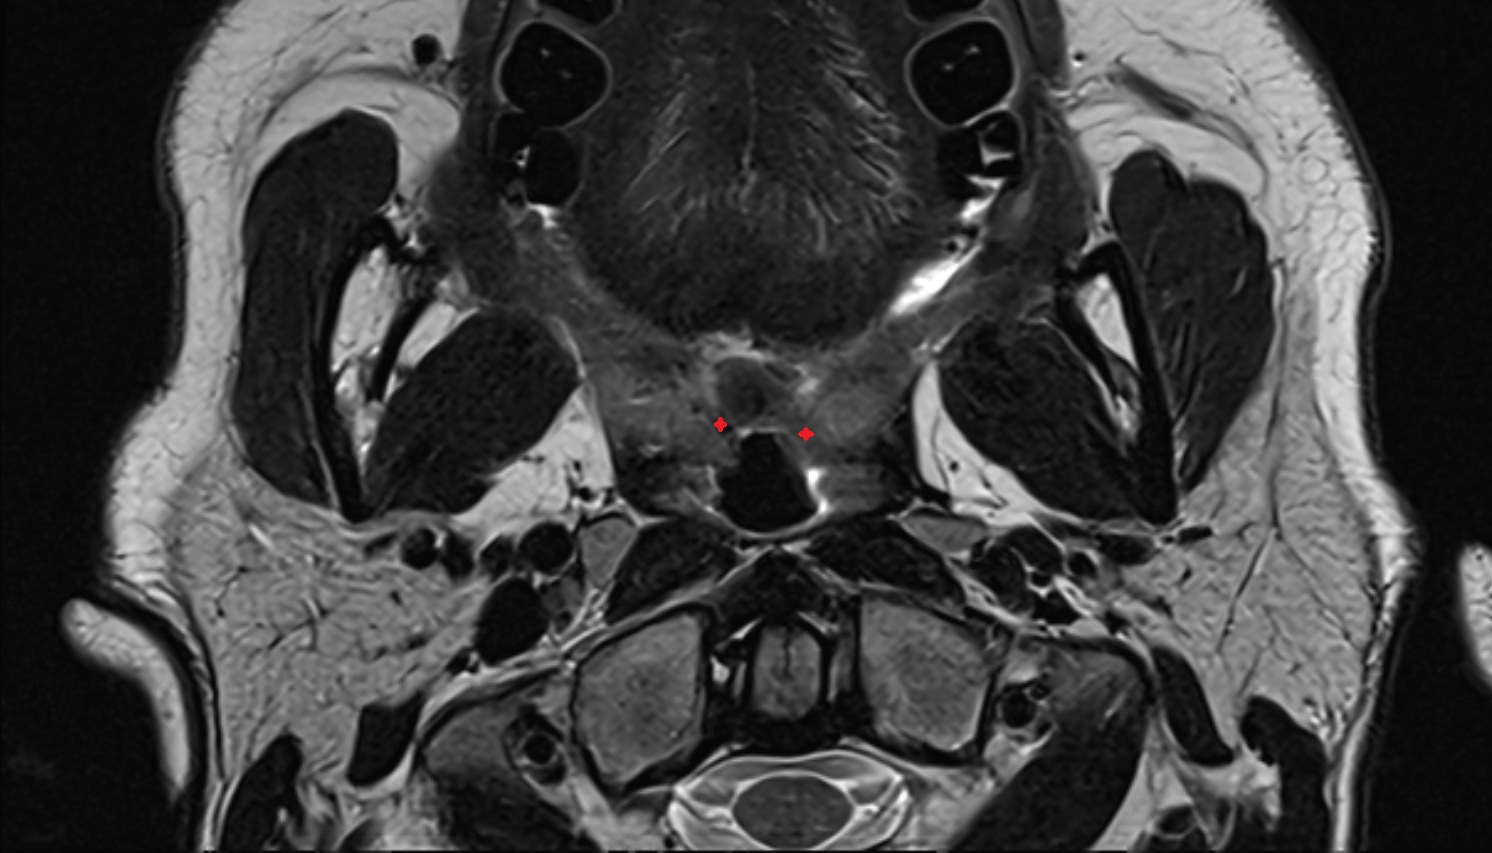

- Peripheral zone of prostate

- Anterior Fibromuscular Stroma of prostate

- Central zone of prostate

- Transitional zone of prostate